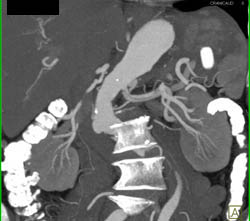

Splenic Artery Aneurysm